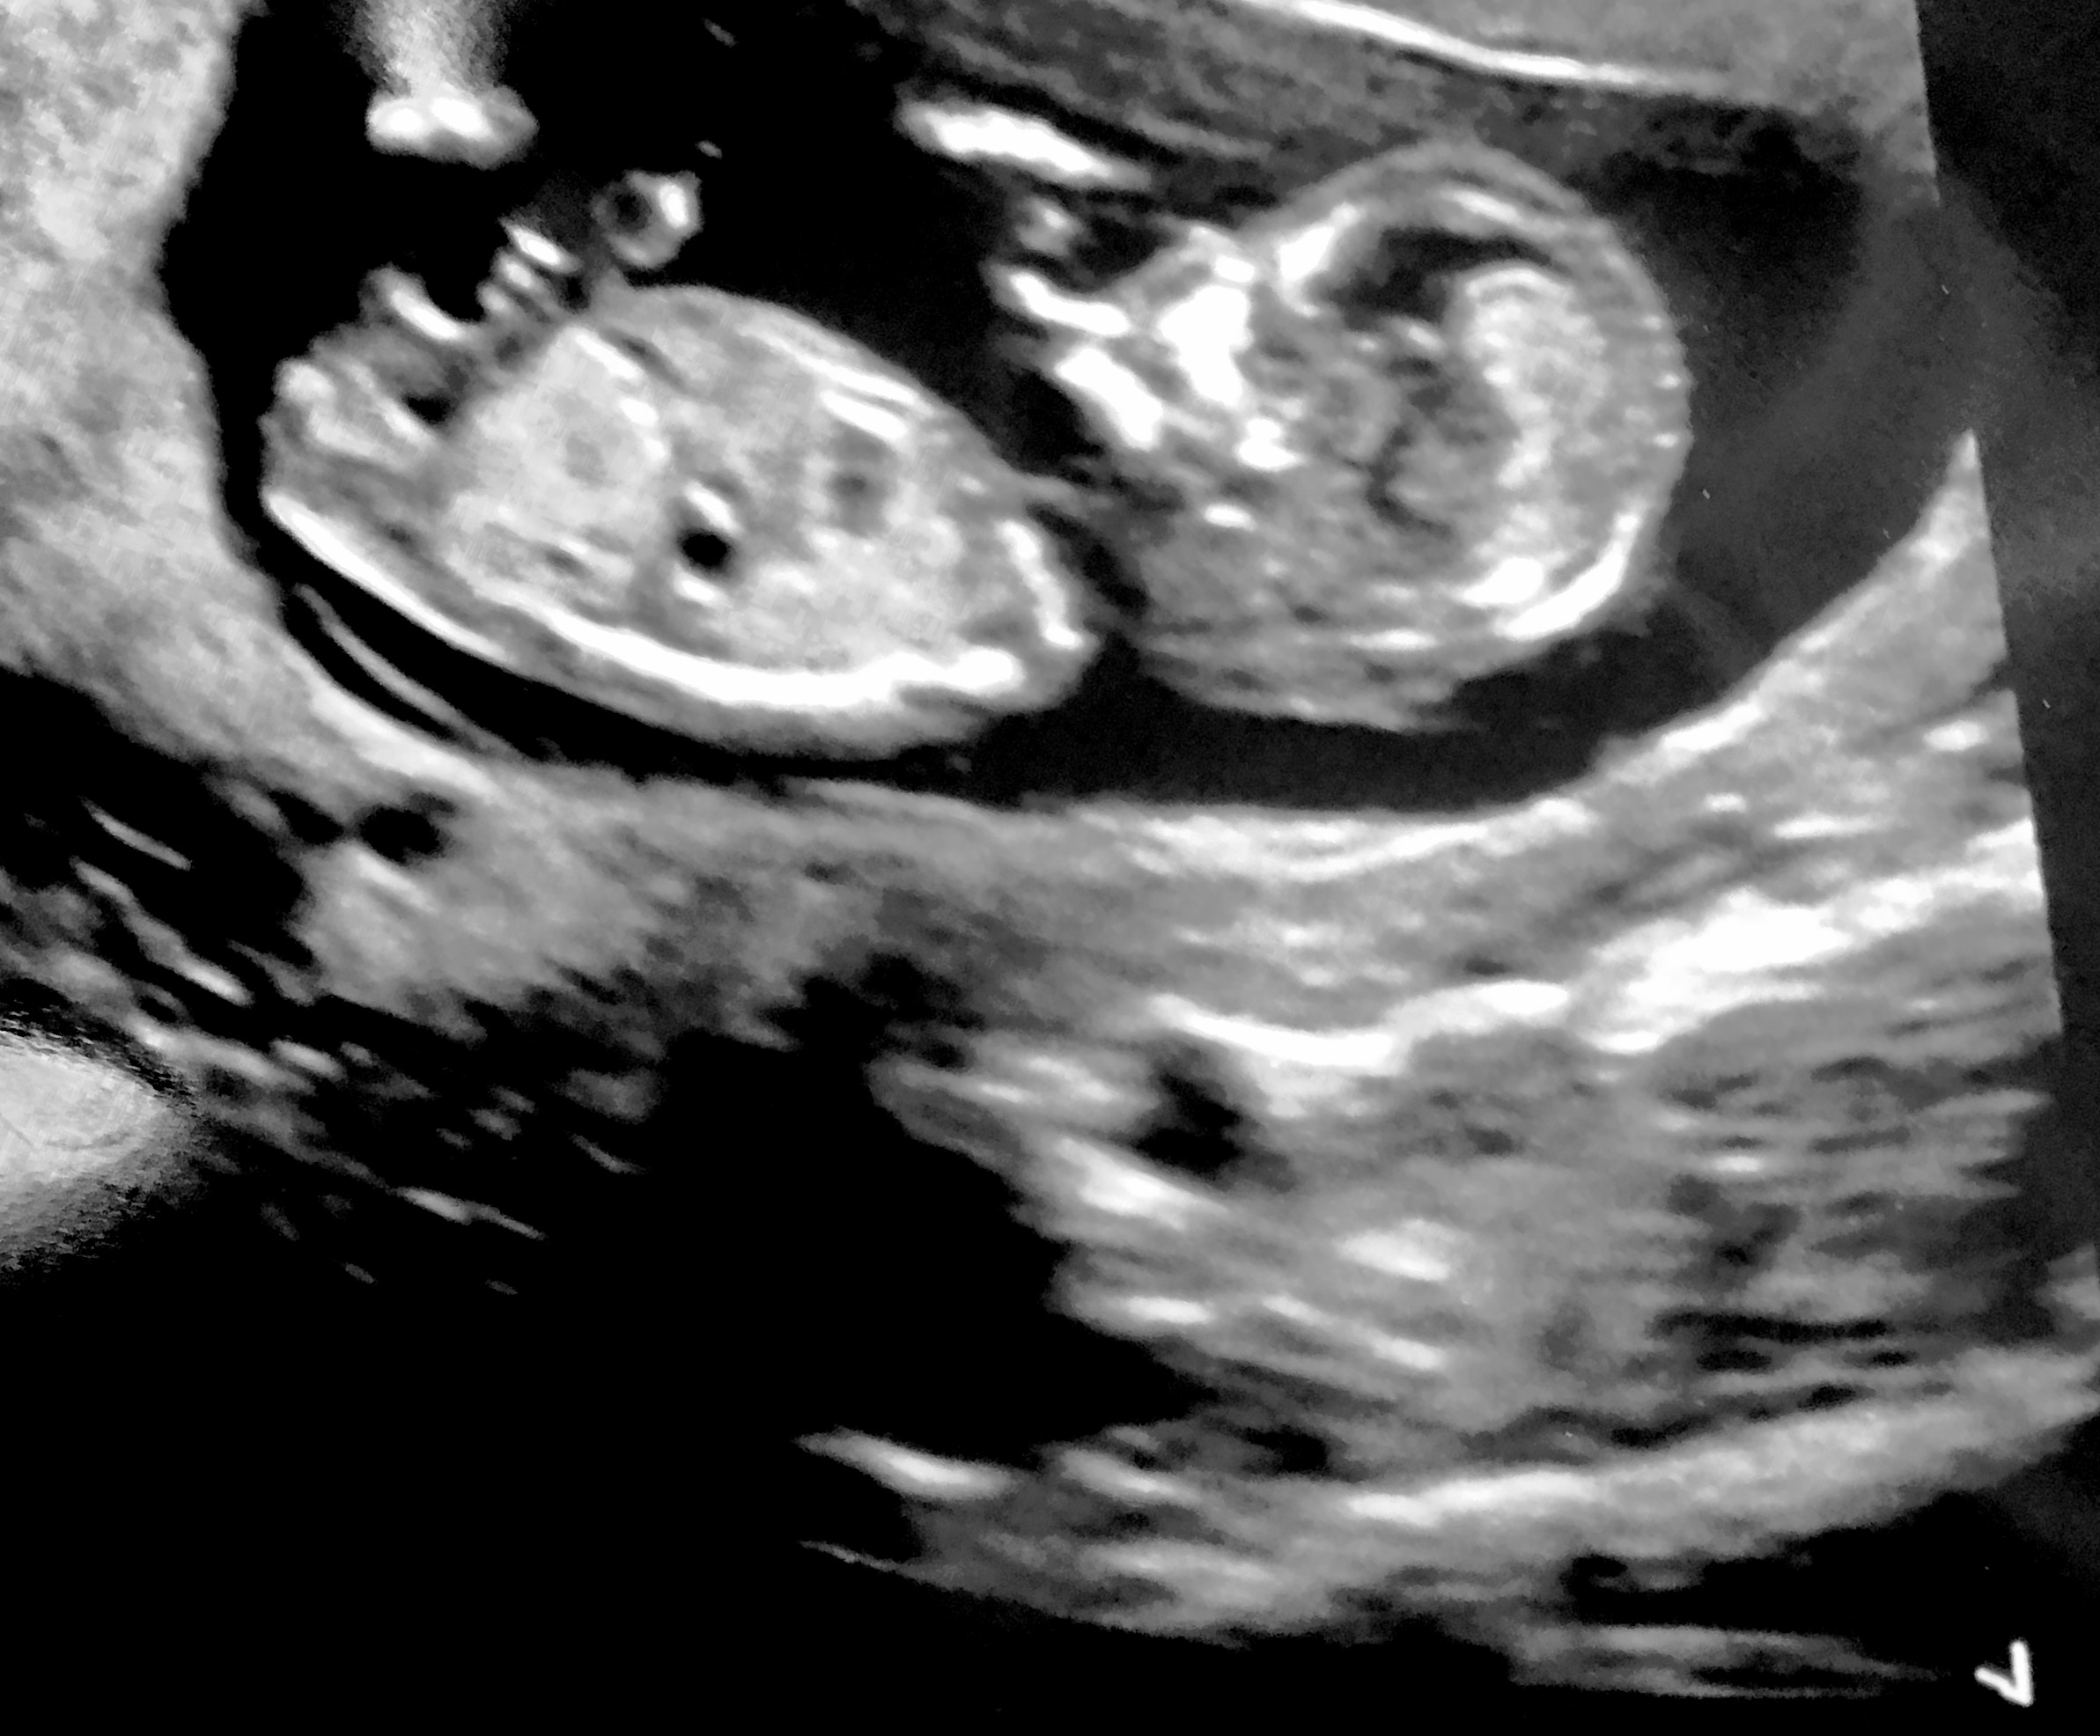

What do you think girl or boy xxx

Little hard to guess this one.. gonna give a blue lean because I think nub is pretty thick though it's short and kind of bent like it may be on the rise.. depends how far along you are. If you are 13 weeks + that would make this more girly less boy lean from me

How many weeks was this taken?

13 weeks x

Could be girl, but I agree with Burakoam's reasoning, so there is a possibility of boy also. Any more pics? Video?